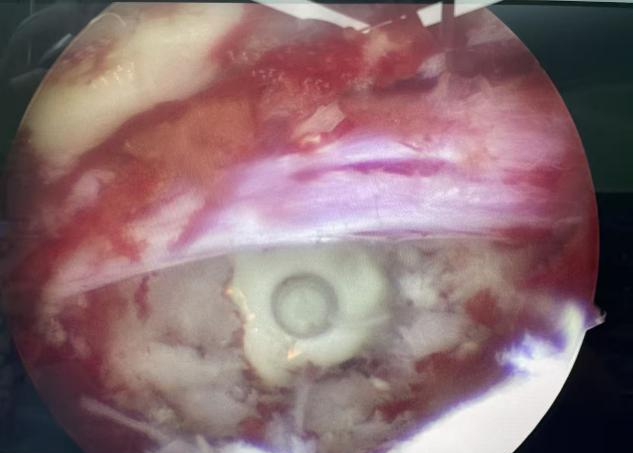

50歲的游先生因長期勞損,飽受腰痛與下肢放射痛折磨,保守治療無效,又因顧慮傳統(tǒng)手術創(chuàng)傷大、需植入螺釘而遲遲未決。我院脊柱團隊為其施行UBE下單側(cè)入路雙側(cè)減壓+椎間盤摘除+神經(jīng)根松解術,手術僅耗時50分鐘,術后24小時即可下床,3天出院,1個月后順利重返工作崗位。 內(nèi)鏡下減壓后影像 術后切口 病例二:高齡多病患者的“安全之選” 76歲的徐老先生患有嚴重腰椎管狹窄伴滑脫,合并高血壓、糖尿病,手術風險極高。經(jīng)多學科協(xié)作,團隊采用UBE技術為其完成減壓、復位、融合與內(nèi)固定,術中出血僅30毫升,無并發(fā)癥發(fā)生。術后第3天,老人已能下地行走,一周出院,家屬特贈錦旗致謝。 內(nèi)鏡下置入融合器 術后切口 術后DR片見滑脫已復位 病例三:復雜結(jié)核感染患者的“精準施治” 72歲的劉奶奶曾因椎體骨折接受骨水泥手術,后確診腰椎結(jié)核伴椎管內(nèi)膿腫,且體質(zhì)虛弱、伴有低氧血癥與貧血。團隊果斷采用UBE行椎管減壓+膿腫清除+骨水泥取出術,以微小切口解決重大隱患,術后患者疼痛顯著緩解,恢復良好。 術中取出椎管內(nèi)干酪樣膿腫 術中取出的骨水泥